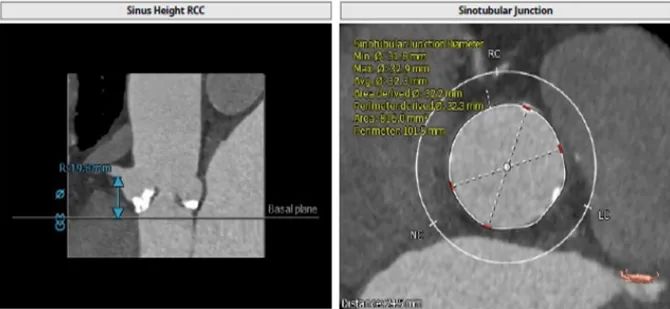

根部解刨

患者为三叶瓣,重度钙化,瓣环29.1 mm,LVOT28.6 mm,预计瓣口开口29.1 mm,STJ 32.3 mm,窦部空间大,左右冠高度分别为16.2 mm和19.8 mm,预计24mm球囊预扩。